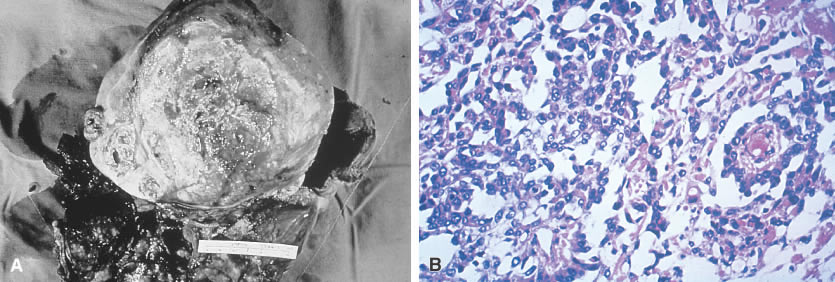

Grossly, dysgerminomas are rubbery, gray, smooth, or bosselated and are surrounded by a dense capsule (Fig. 1A). The cut surface is soft and homogeneous and has a brainlike consistency (Fig. 1B). Tumors range in diameter from several centimeters to 50 cm. The rate of bilateralism is reported to be 5% to 20%.

Fig. 1. Dysgerminoma. A. In situ picture of a unilateral dysgerminoma shows it is bosselated and surrounded by a dense capsule. B. Grossly, a cut surface of this dysgerminoma reveals a yellow-tan, soft, homogeneous, and brainlike consistency. C. Histologic picture of a dysgerminoma shows cells are analogous to the undifferentiated germ cells of an embryonal gonad (i.e., well-defined clusters of cells separated by a fibrovascular system, infiltration [lymphocytes]).

The histologic picture of dysgerminomas is analogous to that of undifferentiated germ cells of the embryonal gonad. These well-defined clusters of cells are separated by fibrous tissue septa with lymphocytic infiltration and an occasional Langhans’ giant cell (Fig. 1C). Although no single pathologic factor is related directly to prognosis, a marked inflammatory response suggests a good immunologic reaction in the tumor. Marked cellular atypia, frequent mitosis, and mixtures with more lethal germ cell tumors yield a poorer prognosis.

On gross examination, primary choriocarcinomas are hemorrhagic and friable. Microscopically, they consist of cells resembling syncytiotrophoblasts and cytotrophoblasts, with extensive areas of hemorrhage and necrosis (Fig. 5).

Fig. 5. Choriocarcinoma. Microscopic view of nongestational choriocarcinoma reveals cells resembling syncytiotrophoblasts and cytotrophoblasts. There is usually extensive hemorrhage and necrosis.